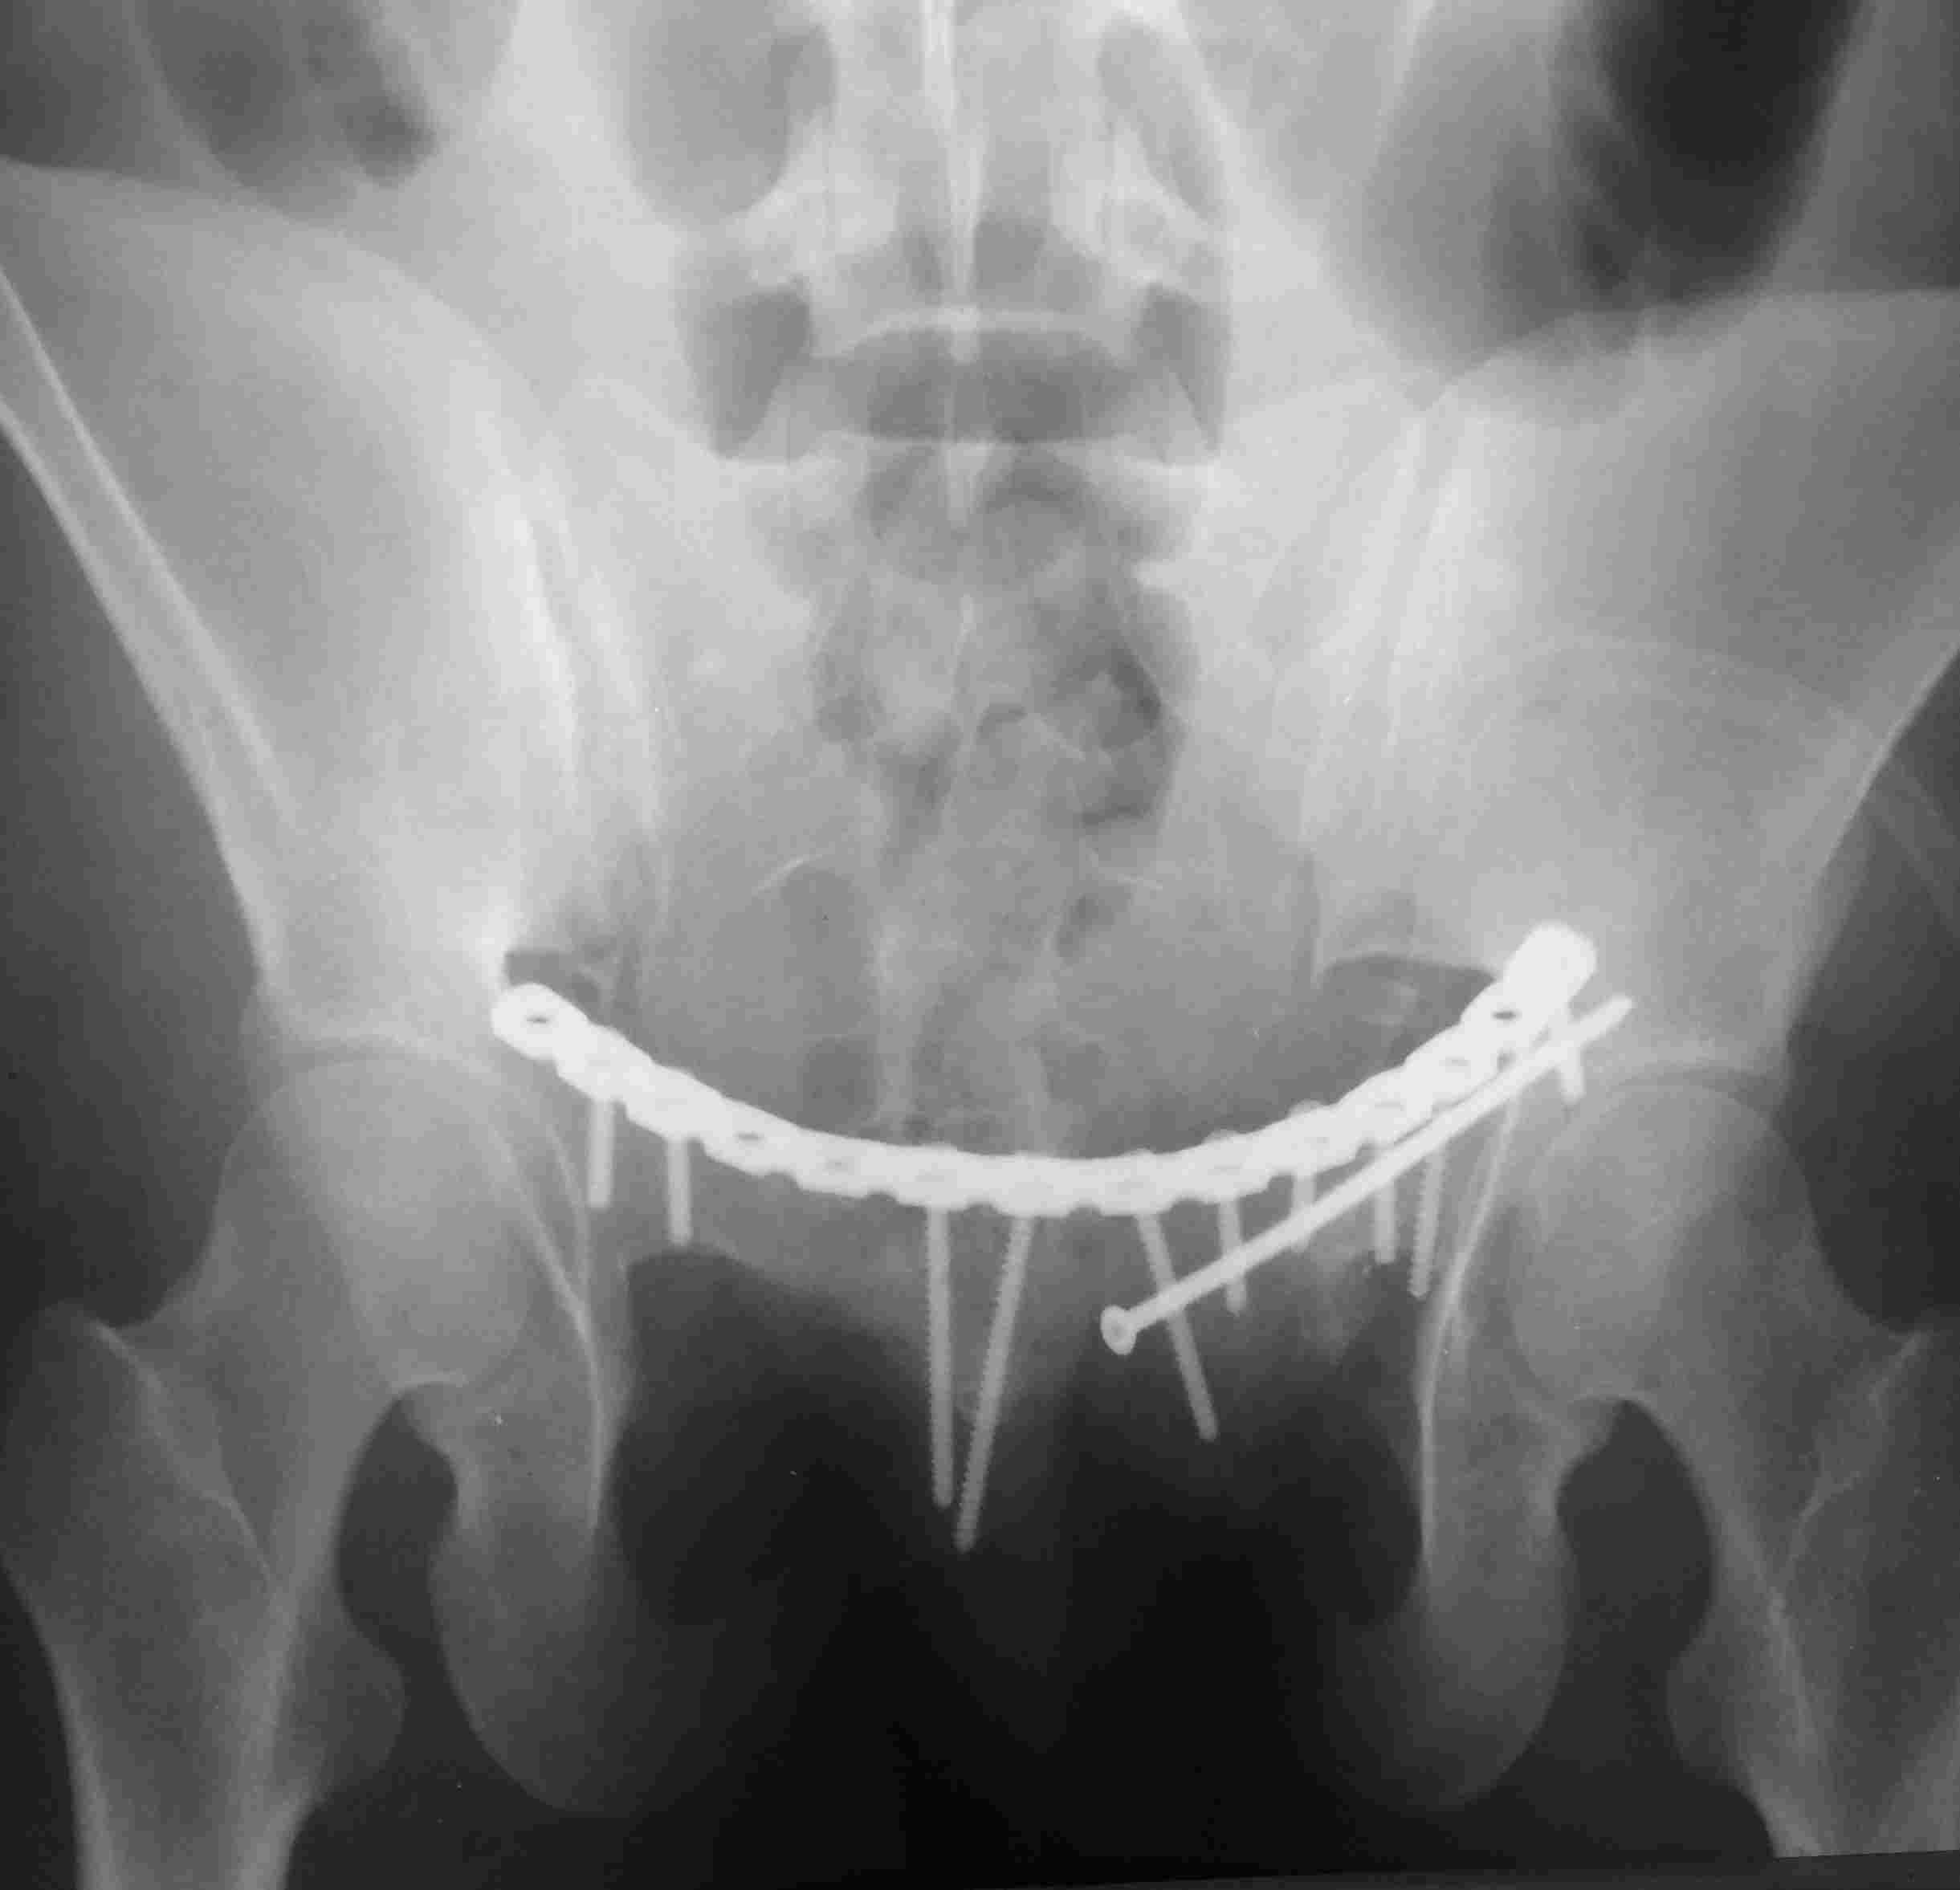

Постоп. Верхняя ветвь возле шейки мочевого пузыря, нижняя так же где-то глубоко в мышцах, ротирована. Обе практически лишены кровоснабжения. лонное сочленение фактически свободно лежащее, справа почти целое, но ветви сломаны возле него. Слева часть лонного сочленения цела на 2/3. интраоперационно подвижность правой половины таза. Постоп все стабильно, но все же планирую дополнительно провести IS винт справа.

PS Нижнюю ветку нормально зафиксировать не получалось зафиксировать, уложил ее в виде чипсов туда, где она примерно была и вдоль верхней ветви слева